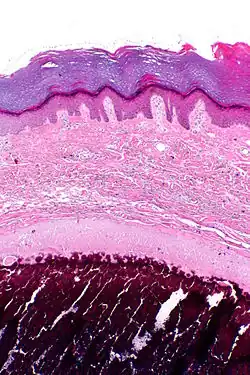

![]() Microfotografía de una biopsia de piel afectada por calcinosis cutis. | ||

En medicina, se entiende por calcinosis cutis o calcinosis cutánea, al depósito de sales de calcio en la piel o el tejido subcutáneo. Puede estar ocasionada por diferentes enfermedades.[1][2]

La calcinosis se caracteriza por el depósito de sales insolubles de calcio, fundamentalmente cristales de hidroxiapatita, en los tejidos blandos. Si el depósito se realiza en la piel o el tejido subcutáneo, el fenómeno recibe el nombre de calcinosis cutis. La causa por la que se depositan las sales de calcio depende de la entidad que origina el mal, siendo el mecanismo no bien conocido. En los enfermos de dermatomiositis, por ejemplo, se cree que las células musculares resultan dañadas por un proceso inflamatorio, lo que hace que las mitocondrias liberen calcio al exterior de la célula, el cual posteriormente se deposita en la piel.[1][2]